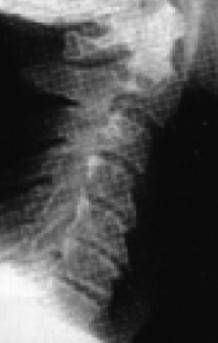

А что в действительности имеем мы? Обычно с возрастом наш позвоночник начинает деформироваться, «проседать», менять статику. В результате небольшой физиологический изгиб гипертрофируется, и шейные позвонки начинают проваливаться внутрь шеи, что особенно интенсивно происходит при «сидячей» работе.

Рис. 13б. Гиперлордоз шейного отдела